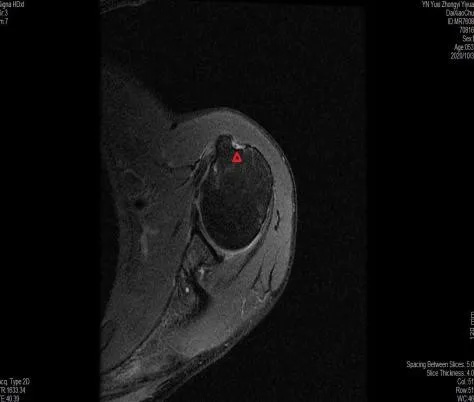

近日,一名53歲的壯漢因?yàn)樘嶂匚锢瓊笊媳?,?dǎo)致左肩及左上臂疼痛,同時在屈肘時在上臂出現(xiàn)形似“大力水手”的腫塊,受傷后到我院骨傷二科(關(guān)節(jié)與運(yùn)動醫(yī)學(xué)科)門診就診,予行左肩及左上臂核磁共振檢查結(jié)果顯示:左肱二頭肌長頭肌腱斷裂,這就是我們?nèi)粘I钪鞋F(xiàn)實(shí)版的大力水手征,由于肌腱的斷裂導(dǎo)致這名壯漢左上臂一定力量的減弱。

肱二頭肌攣縮征象

肱二頭肌斷裂征象